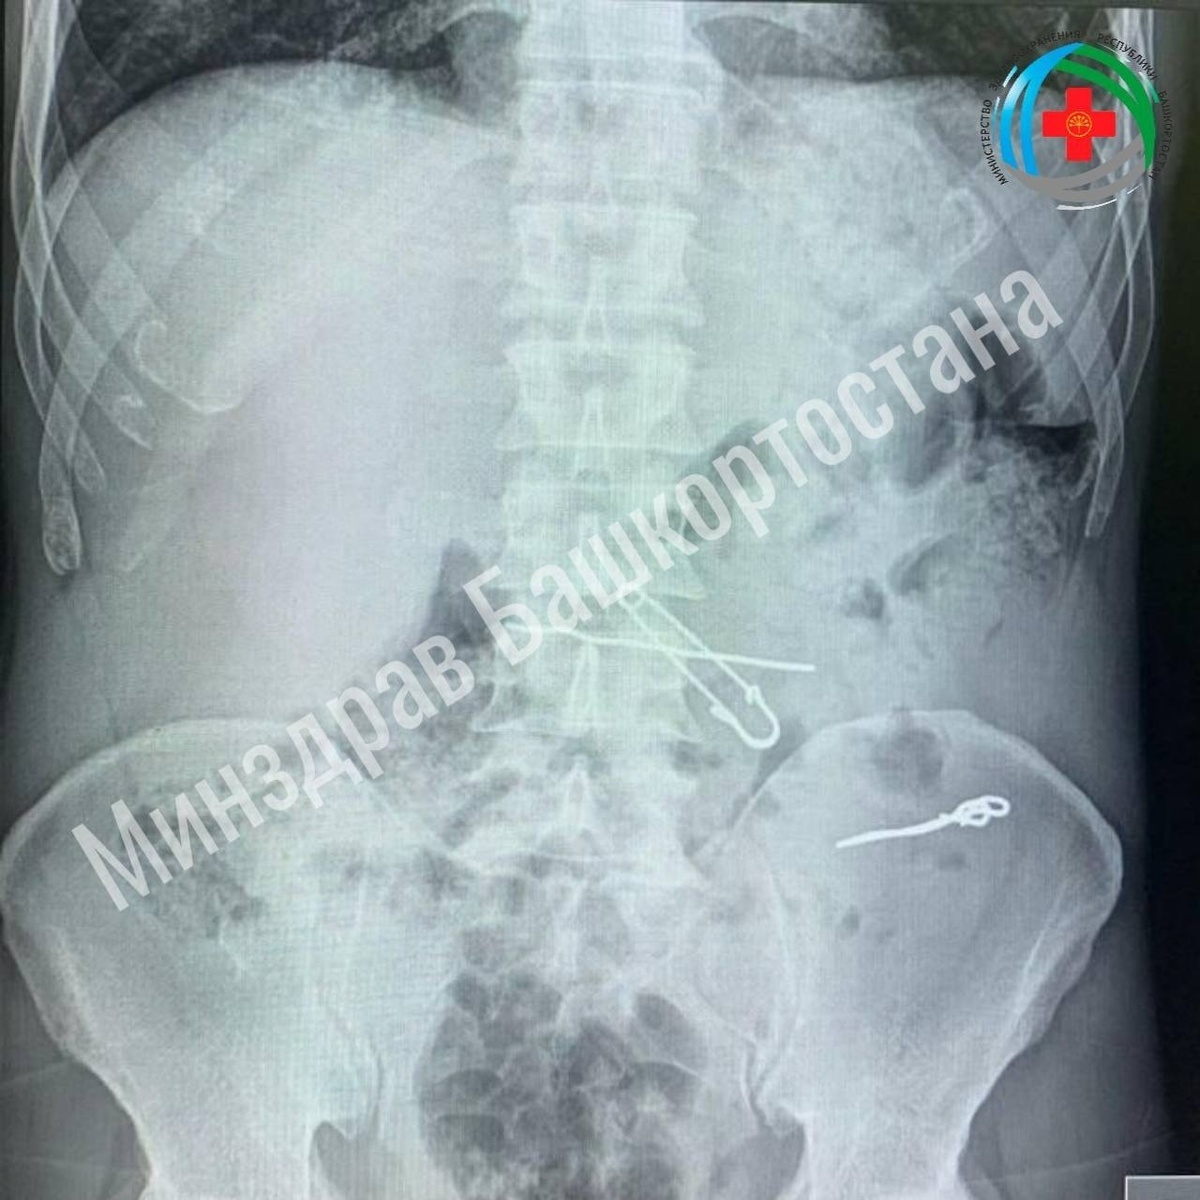

В Уфе взрослый мужчина проглотил ключи, скрепки, булавку и проволоку. Пациент сам обратился в приемный покой больницы скорой помощи с жалобами на боли в животе. Во время обследования врачи обнаружили в толстой кишке проволоки, скрепки длиной 47, 62 и 90 мм. В желудке же находились булавка и проволока. Мужчину госпитализировали в отделение гнойной хирургии и провели операцию, все инородные тела достали. Пациент восстановился и выписался из больницы. Историю в своем телеграм-канале опубликовал министр здравоохранения Айрат Рахматуллин. Читайте также: Житель Уфы едва не ослеп от болгарки